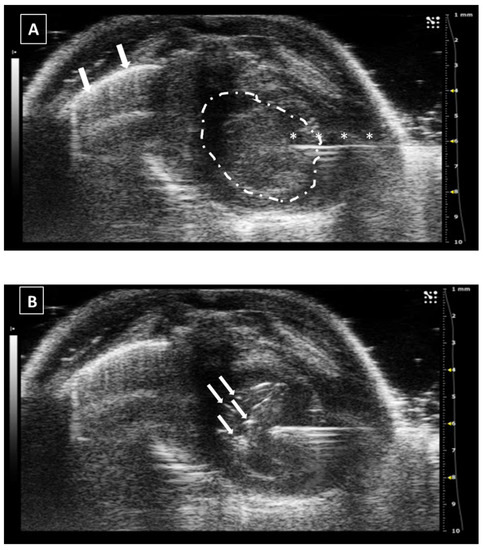

In the same way as the liver and spleen, the kidney biopsy can be performed following the same approach as the injection but pulling the needle plunger instead of pushing it down. Multiple samples can be collected in both the cortical and medullar areas of the organ. An example of a renal injection is shown in Figure 7.

Figure 7. Intrarenal injection. (A) Injection of the needle into the kidney. Needle is marked with white asterisks and the kidney is surrounded by a dashed line. The injection is performed in the medullar zone of the organ. (B) Administration of the fluid, that is marked with a white asterisk. Images obtained at 40 MHz frequency.